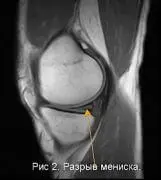

На рисунке № 2 представлена картина повреждения мениска — выглядит в виде широкой светлой линии пересекающей практически весь мениск.